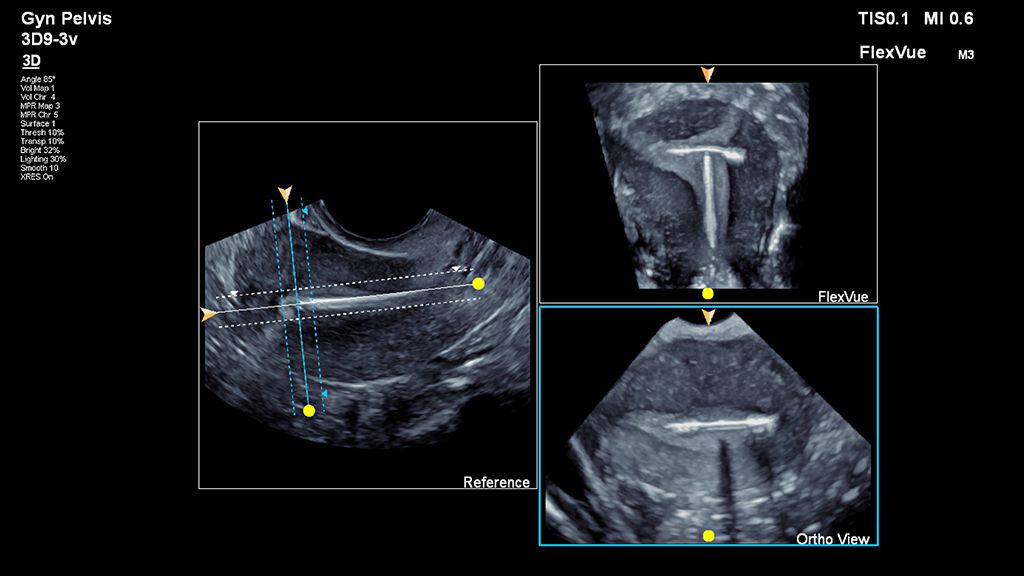

Demonstrated results using FlexVue

It (FlexVue) takes all of the complications out of MPR and manipulation of a surface-rendered volume. By deploying a straight line or a curved trace or continuous trace, we can take a curved image, flatten it out and make it a single planar image.